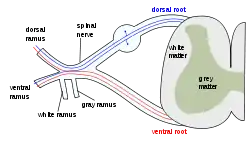

The formation of the spinal nerve from the posterior and anterior roots Scheme showing structure of a typical spinal nerve.

Scheme showing structure of a typical spinal nerve.